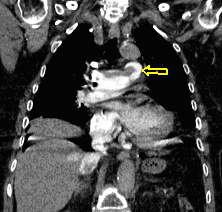

60 year old man, secondary pulmonary lesions due to kidney tumor, underwent target therapy.

Lobulated nodule in the left lung, associated with the pleura dorsobasally.

Lobectomy because of right lung adenocarcinoma, (brain metastasis). (by the contribution of Zsuzsanna Monostori, MD, PhD)